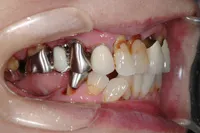

■治療前:奥歯が無いため噛み合わせが深く下の歯が全く見えない

噛み合わせが低いため全体的に歯が削れている

■治療後:下顎 左下5・6番、右下4・6番にインプラント治療

その他の歯に補綴治療をしたことにより、奥歯もしっかりと咬むことができ、奥歯ができたことにより噛み合わせも上がって下の歯も見えるようになり、審美的にも改善された

| 主訴 | 歯科治療をしても歯がすぐに欠けてしまう 奥歯が無いため、奥歯で咬めない |

| 治療方法 | インプラント治療 + 補綴治療 |

| 治療期間 | 約1年 |

| 通院回数等 | 約20回 |

| 費用 | 約250万円(税込) |

| リスク・副作用 | 術後の腫れ・痛み |